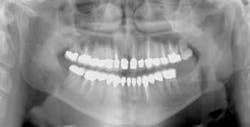

The preceding characteristics are often negated when some other conditions are considered. The factors described in the following discussion may override apparently adequate tooth structure remaining and indicate post placement is required (see Figs. 1 and 2).